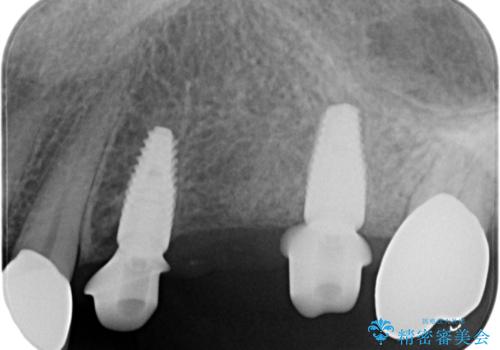

複数の奥歯の欠損 インプラントによる咬合機能回復

- 105.6万円(インプラント×2・チタンカスタムアバットメント×2・ジルコニアクラウン×3・仮歯×3)費用は治療当時の料金となります

しっかりと咬合機能の回復がなされ、また食事を楽しんでいただけるようになりました。